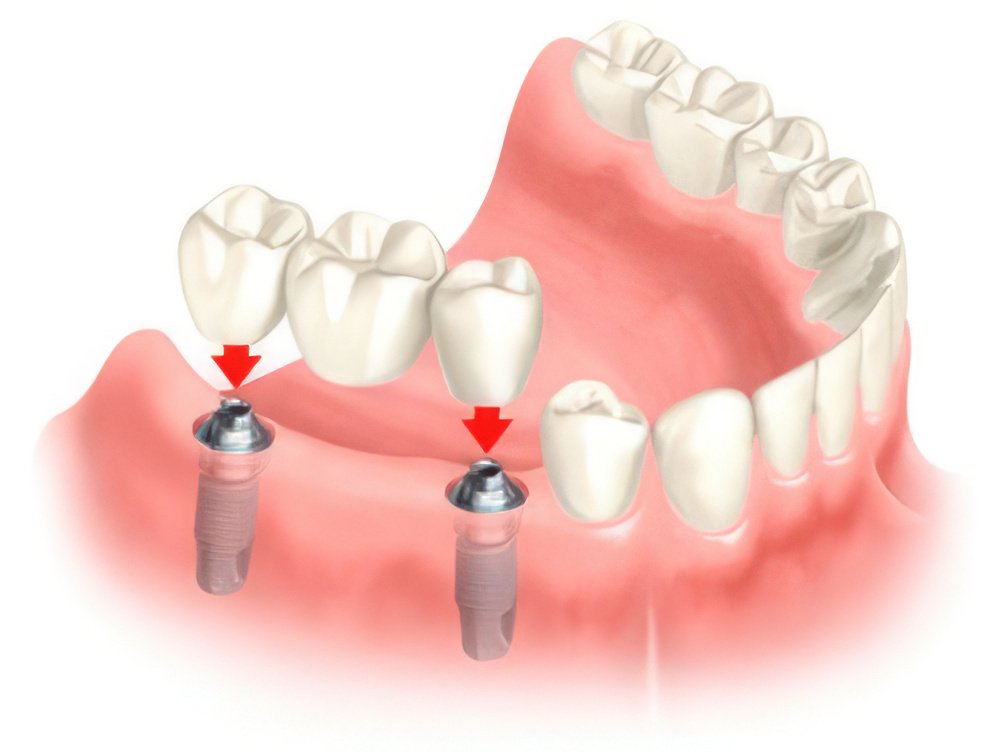

Современные коронки на зубные импланты: виды и фото-примеры